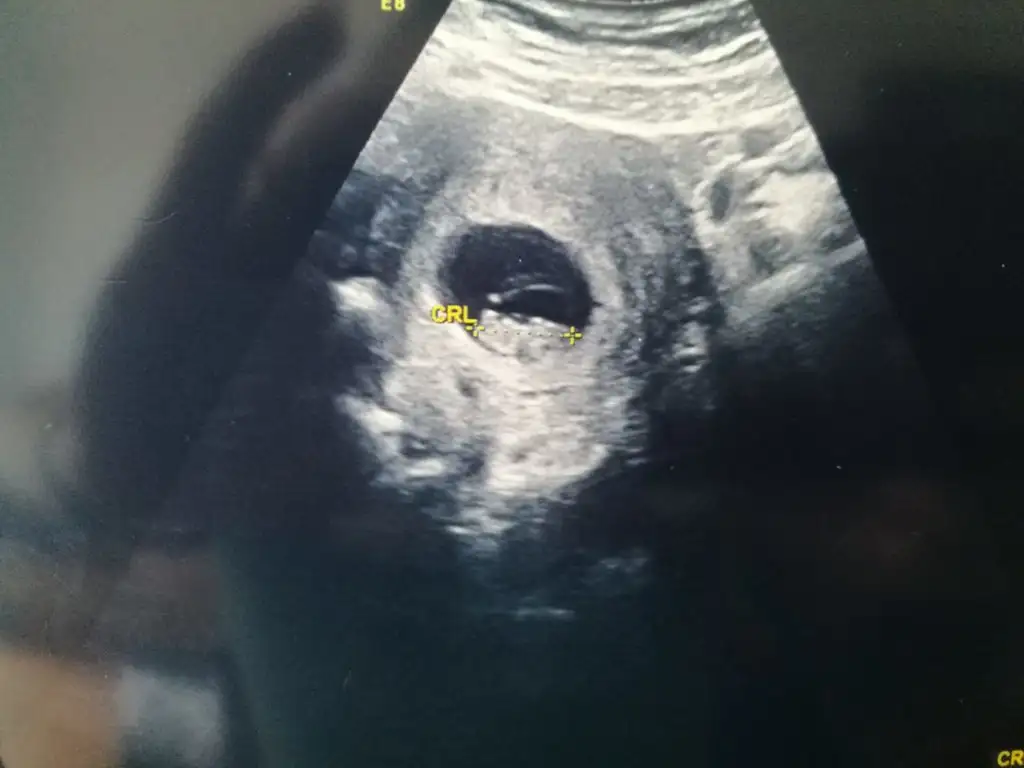

Bence erkek gibiEki Görüntüle 2277371 Buda arkadaşımın bebişi acaba onun Cinsiyeti nedir

9+4 göre erken sekil almış erkek diyorumBende yorum alabilir miyimEki Görüntüle 2218569

Bu dogrumu canm benim 7 haftalik teoriye solda karinda erkek zaten gissedyrdm dr birgun onceerkek ikili testte kiz dedi anlamadk 14 haftalgm ins degsr9+4 göre erken sekil almış erkek diyorum